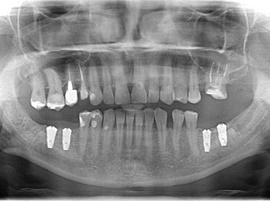

Pacjentka lat 72, od kilkudziesięciu lat chorująca na cukrzyce I typu, obecnie od 10 lat na pompie insulinowej. Profesor medycyny, siostrzenica pacjentki prowadzi swoją ciocię diabetologicznie, pacjentka świadoma zagrożeń przy zabiegach regeneracji kości i implantacji w takim ogólnym stanie zdrowia. Po rekonstrukcji tkanek miękkich i kości osadzono dwa implanty o średnicy 5,0 mm. Na zdjęciu śródzabiegowym widać zadowalające wyniki rekonstrukcji tkanki kostnej. Po upływie kilku miesięcy wykonano nadbudowę protetyczną.

Pacjentka lat 55, od wielu lat użytkowała protezę ruchomą. Przed implantacją dokonano augmentacji kości wyrostka. Sytuacja po zakończeniou leczenia, estetyczna i funkcjonalna, zadowalająca pacjentkę.

Pacjentka po ekstrakcji kilku zębów, z implantacją natychmiastową, odroczoną. Zdjęcie pantomograficzne wykonano pięć lat po implantacji. Widoczna stabilna sytuacja kostna i dziąsłowa.